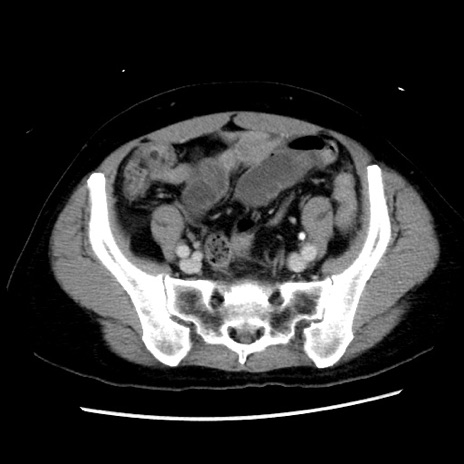

矢状断像